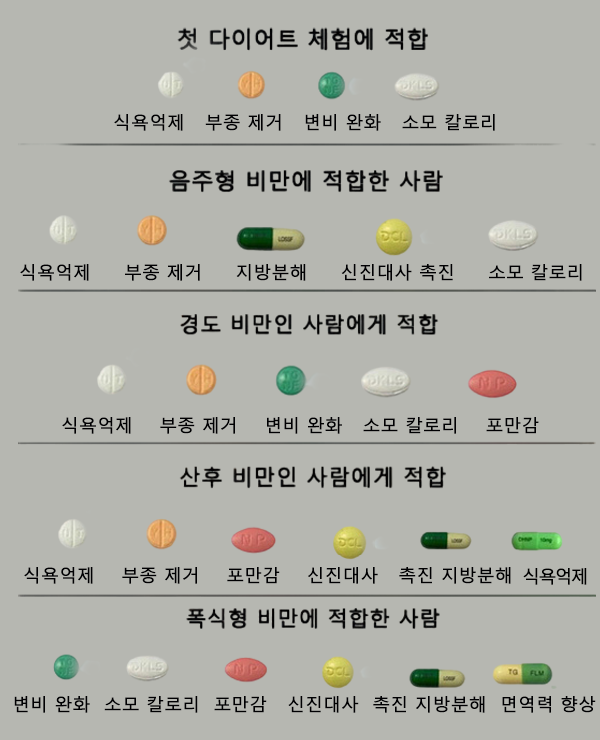

체질별 다이어트 처방약